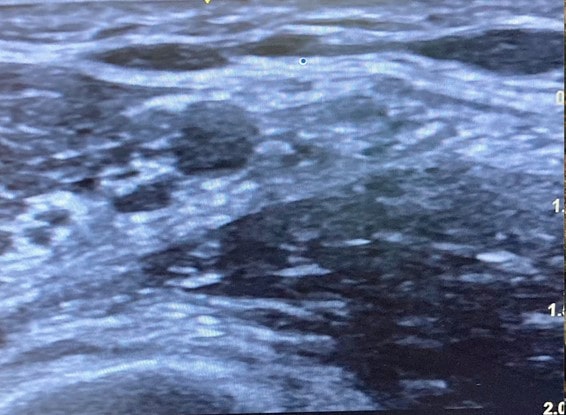

La imagen ecográfica típica del espacio axilar es la que se observa aquí:

- Localizamos la arteria axilar como una estructura pulsátil, anecoica y de forma circular. En la parte baja de la imagen observaremos una estructura redondeada hiperecogénica que se corresponde al húmero. Lateralmente a la arteria veremos dos estructuras musculares que se corresponden al músculo bíceps y el músculo córaco-braquial. Otras estructuras típicas son el músculo redondo mayor que se localiza profundamente y medial respecto a la arteria y vena axilar.

- Los nervios se van a visualizar de diferentes maneras, siendo la más común la aparición de estructuras hiperecoicas redondeadas u ovales rodeadas de un refuerzo hiperecogénico que corresponde al epineuro, en una disposición como de panal de abejas.